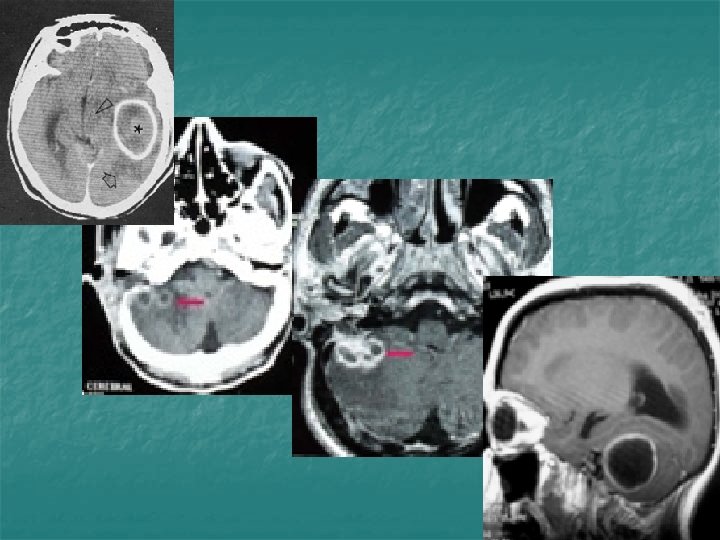

TDM coupe axiale après injection de PDC: Otomastoidite compliquant une OMC cholestéatomateuse droite

Abcès pariétal compliquant une OMC droite cholestéatomateuse

Labyrinthite: Prise de contraste de la cochlée, du vestibule et du fond du CAI

IRM coupe coronale T 1 GADO : comblement de l’oreille moyenne avec lyse du tegmen tympani et prise de contraste méningée